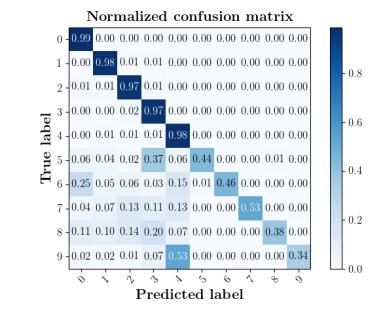

We further compare the performance of MIDNet with and without unlabeled data on the target domain. Here, the with unlabeled data setting utilizes the training data containing labeled data and unlabeled data, while the without unlabeled data setting only uses the labeled data. The confusion matrices in Fig. 8(a) show the effectiveness of unlabeled data in the proposed method, for example, the classification accuracy of in MIDNet (e.g., 4CH and Lips) improves when integrating unlabeled data.

The confusion matrices in Fig. 8(b) show the effectiveness of unlabeled data in the proposed method. The classification accuracy of Femur and Lips in MIDNet improves when using unlabeled data.

We further compare the performance of MIDNet in a semi-supervised setting and a fully-supervised setting. Here, the semi-supervised setting utilizes the training data containing labeled data and unlabeled data, while the fully supervised setting only uses the labeled data. The confusion matrix in Fig. 14 shows the effectiveness of unlabeled data in our proposed method, for example, the classification accuracy of greatly improves when integrating unlabeled data (semi-supervised).